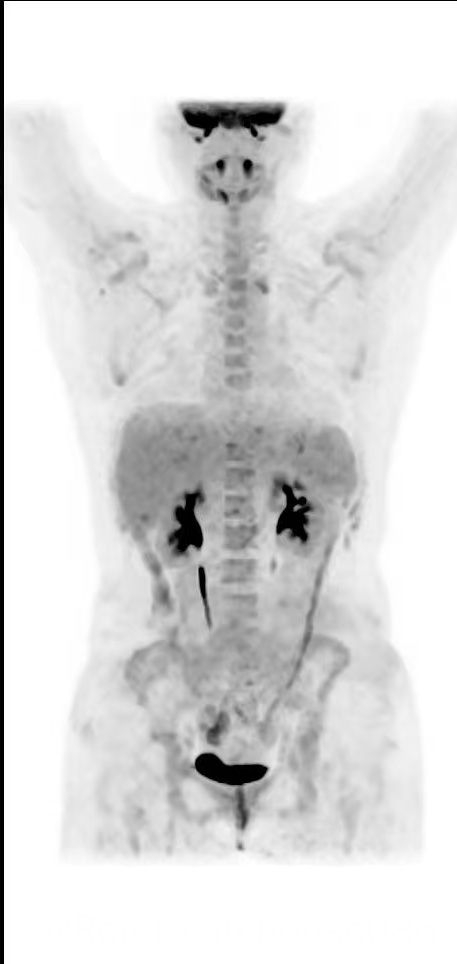

今天是我重生的75天,顺利康复出院了。PET CT这张照片是我最期盼最爱的一张照片!今天的CR喜报是我和爸爸、妈妈以及弟弟共同打赢的生死契约,也凝结着曹星玉主任、柳喜洋主任、薛松主任、祁大夫及整个医疗团队的智慧与心血。